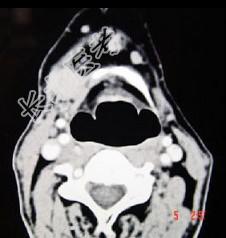

- 单项选择题男,45岁, 右侧颌下扪及一包块约4个月,无痛, PE:包块质硬, 表面欠光整,移动度较差, CT如图所示,最可能诊断为 ( )